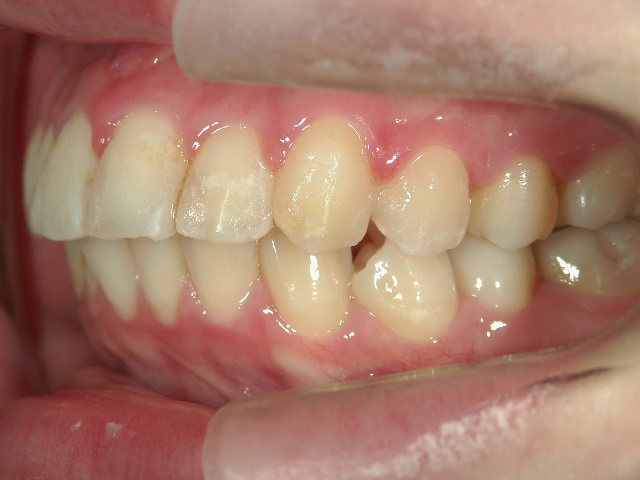

矯正歯科 治療前

no.6_8296_治療前_右.jpgno.6_8296_治療前_正面.jpgno.6_8296_治療前_左.jpg